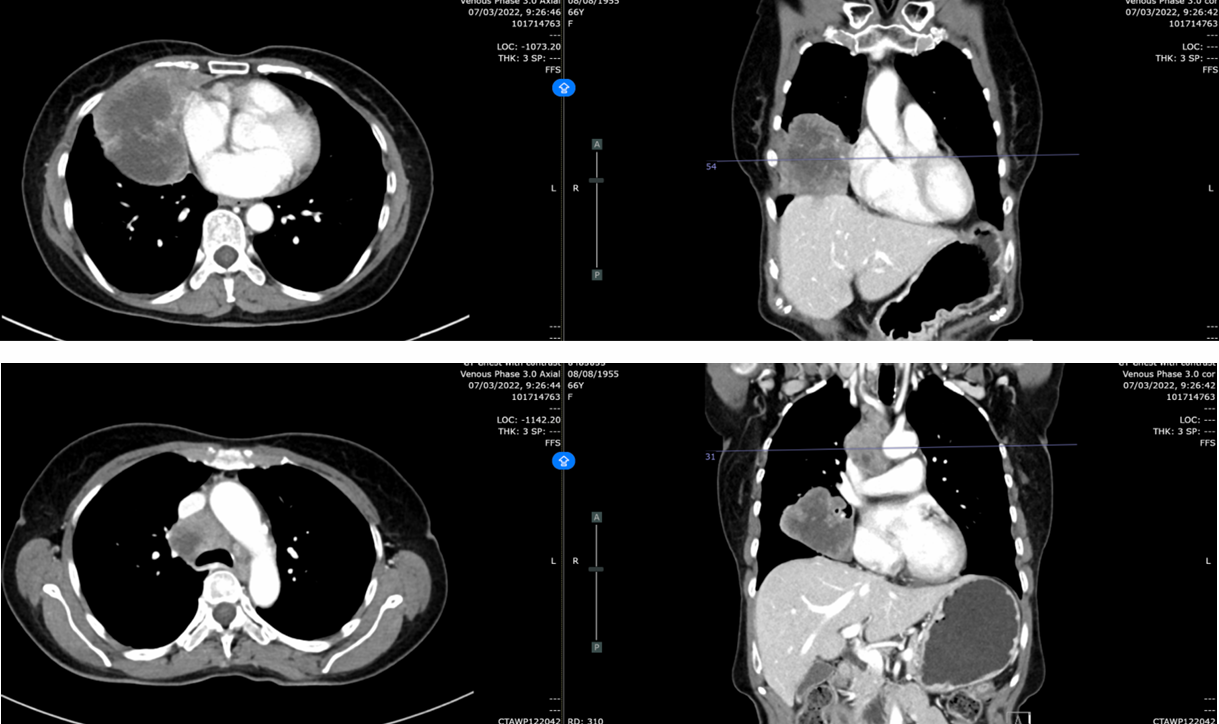

疗效评价:复查CT(2022-07-11),肿块从9.4cm缩小至5.4cm,评估为部分缓解(PR),肺内转移灶及纵隔淋巴结均较前缩小。

复查CT(2022-11-29):肿块5.2cm(缩小),仍维持PR状态,肺内结节缩小至0.5cm,淋巴结部分缓解并出现坏死性改变。

复查CT(2023-02-21):肿块5.3cm,仍维持PR状态。

复查CT(2023-05-19):肿块4.3cm,淋巴结缩小至0.8cm,无肝/肾上腺转移。